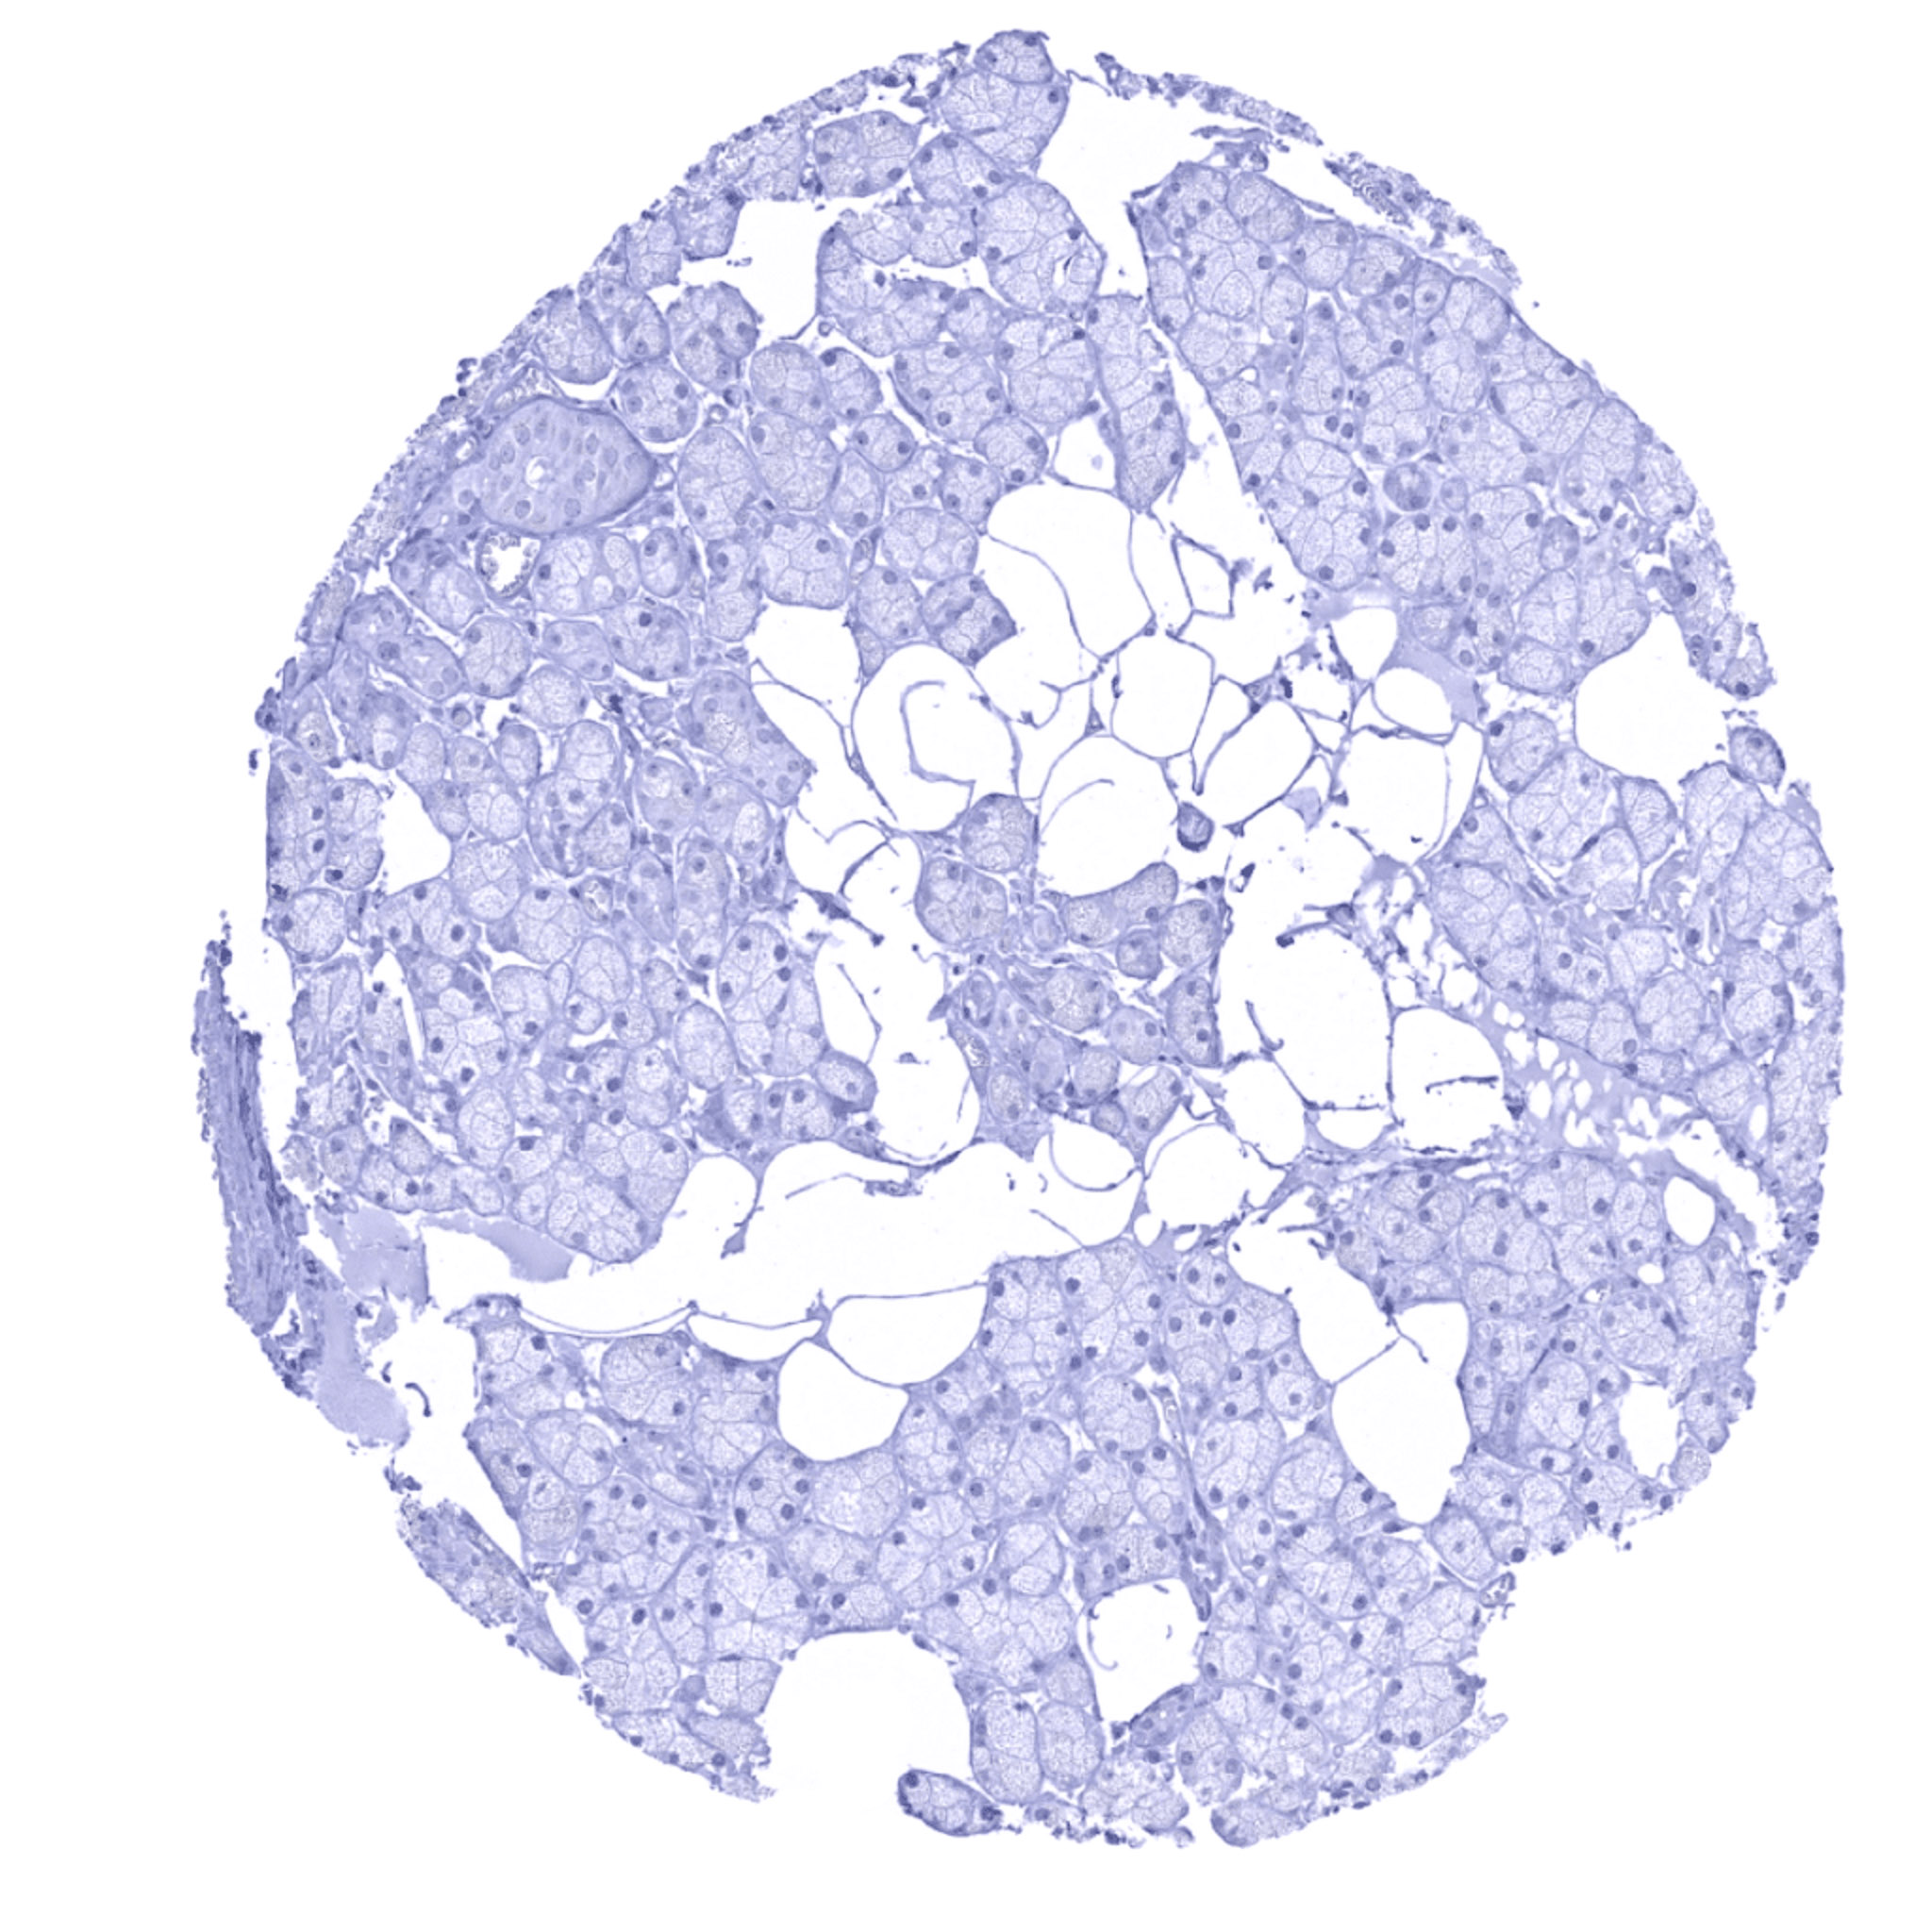

Thyroid gland